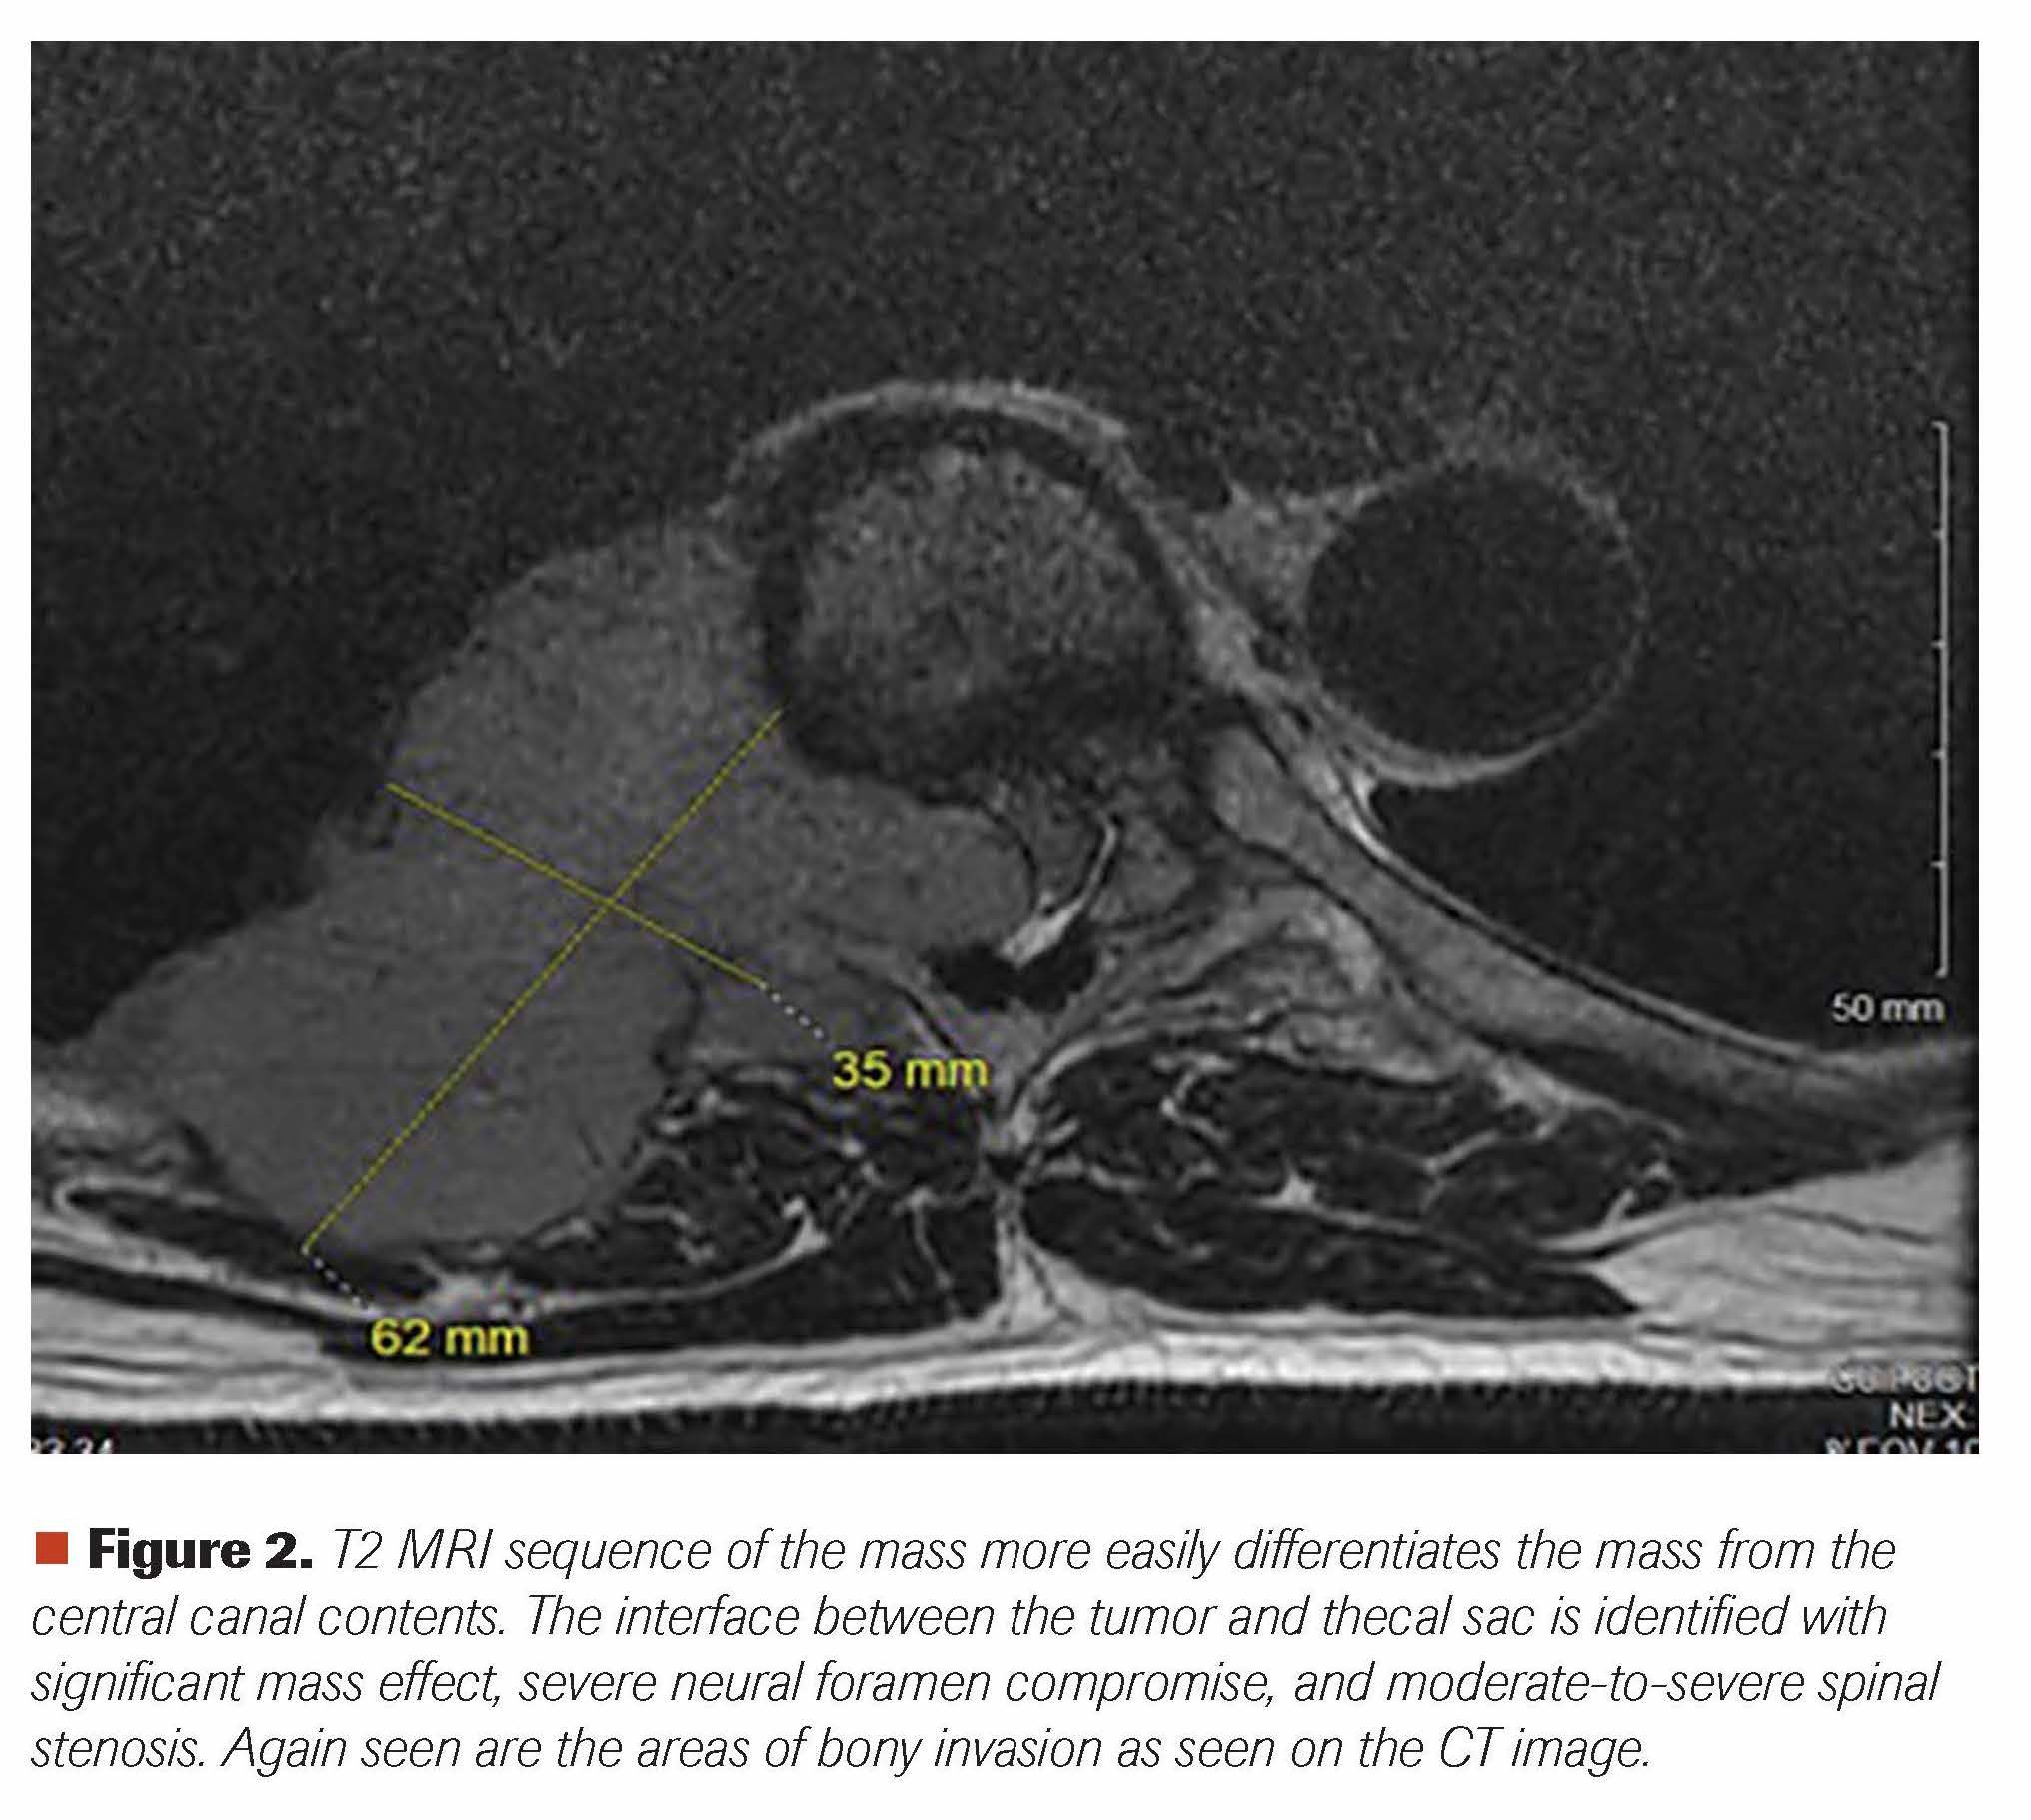

A man aged 65 years presented with right-sided lower thoracic back pain of 1-month duration; it was brought upon by pushing a sliding door in his garage. While it was initially a sharp pain, it transformed into a dull continuous ache radiating to his right rib and right hemithorax. He thought he pulled a muscle and saw a chiropractor, but he received no relief despite 5 chiropractic treatment sessions. During all this time he did not notice any extremity weakness or bladder or bowel incontinence, but he eighth area. He next saw his primary care provider, and a CT scan of his chest revealed a soft tissue mass measuring 6.2 x 3.5 x 2.8 cm in the posterior mediastinum/posterior chest wall with involvement of the posterior eighth rib and adjacent T8 vertebral body, with extension into the right aspect of the spinal canal (Figure 1). Further evaluation with an MRI of the thoracic spine confirmed the T8 compression and associated soft-tissue mass causing moderate-to-severe central spinal stenosis (Figure 2). A CT-guided biopsy of this large destructive mass revealed sheets of plasma cells (Figures 3 and 4). Further work-up revealed abnormal serum protein electrophoresis with a 3.53 g/dL monoclonal serum paraprotein, abnormal serum immunoglobulins (Ig; 5365 mg/dl; IgA, 23 mg/dL; IgM, 11 mg/dL), abnormal free light chains (λ free light chain, 14.6 mg/L; λ free light chain, 146.2 mg/L; ratio, 0.1), and abnormal λ-2 microglobulin of 4.9 mg/L. Bone marrow aspiration and biopsy revealed plasma cell myeloma comprising 40% of marrow cellularity (Figures 5 and 6). Staging work-up was completed with a PET-CT, confirming large osseous destructive mass at T8 level (Figure 7).

Figure 2. T2 MRI sequence of the mass more easily differentiates the mass from the central canal contents. The interface between the tumor and thecal sac is identified with significant mass effect, severe neural foramen compromise, and moderate-to-severe spinal stenosis. Again seen are the areas of bony invasion as seen on the CT image.